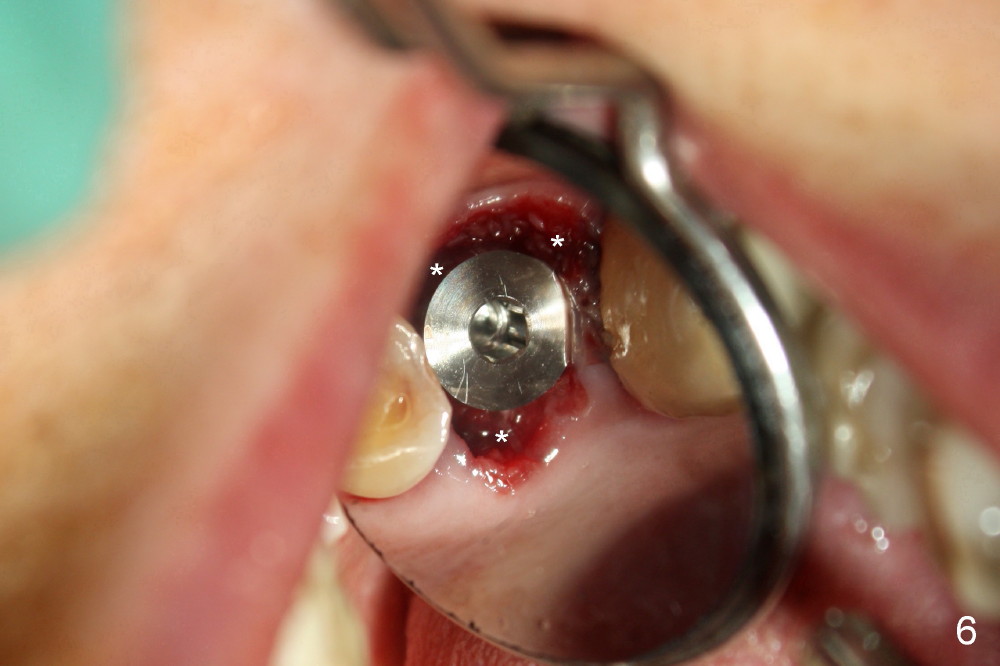

A 66-year-old lady requests restoring a broken tooth (Fig.1). Osteotomy is initiated in a thin septum (Fig.2 (occlusal mirror view) S) by sectioning, drilling and tapping (Fig.3 T). When 7x17 mm tap is removed, the osteotomy is found to form basically in the middle of socket (Fig.4 O). The apical portion of three sockets (Fig.5: MB, P and DB (not labeled) is packed with mixture of autogenous bone and allograft. When a 7x14 mm implant is placed, there are buccal and lingual gaps (Fig.6 *). The latter are bone grafted again (Fig.8 *) and require a coverage. After placement of a 4x3 mm abutment (Fig.7,8 A), an immediate provisional is fabricated (Fig.9 tissue surface view) to cover the remaining sockets (Fig.10 (occlusal mirror view), 11 (buccal view)). The provisional is infra-occlusal, i.e., load-free (Fig.11). The buccal and lingual aspects of the socket are covered by fresh epithelium 8 days postop (Fig.12 <). The implant appears to have osteointegrated 4 months postop (Fig.13). The tooth #16 appears to have shifted mesially. It is difficult to prepare for #15 crown. Luckily the patient agrees to have it extracted because of persistent sensitivity after MO composite. The definitive crown at the site of #15 is cemented 6 months postop (Fig.14).